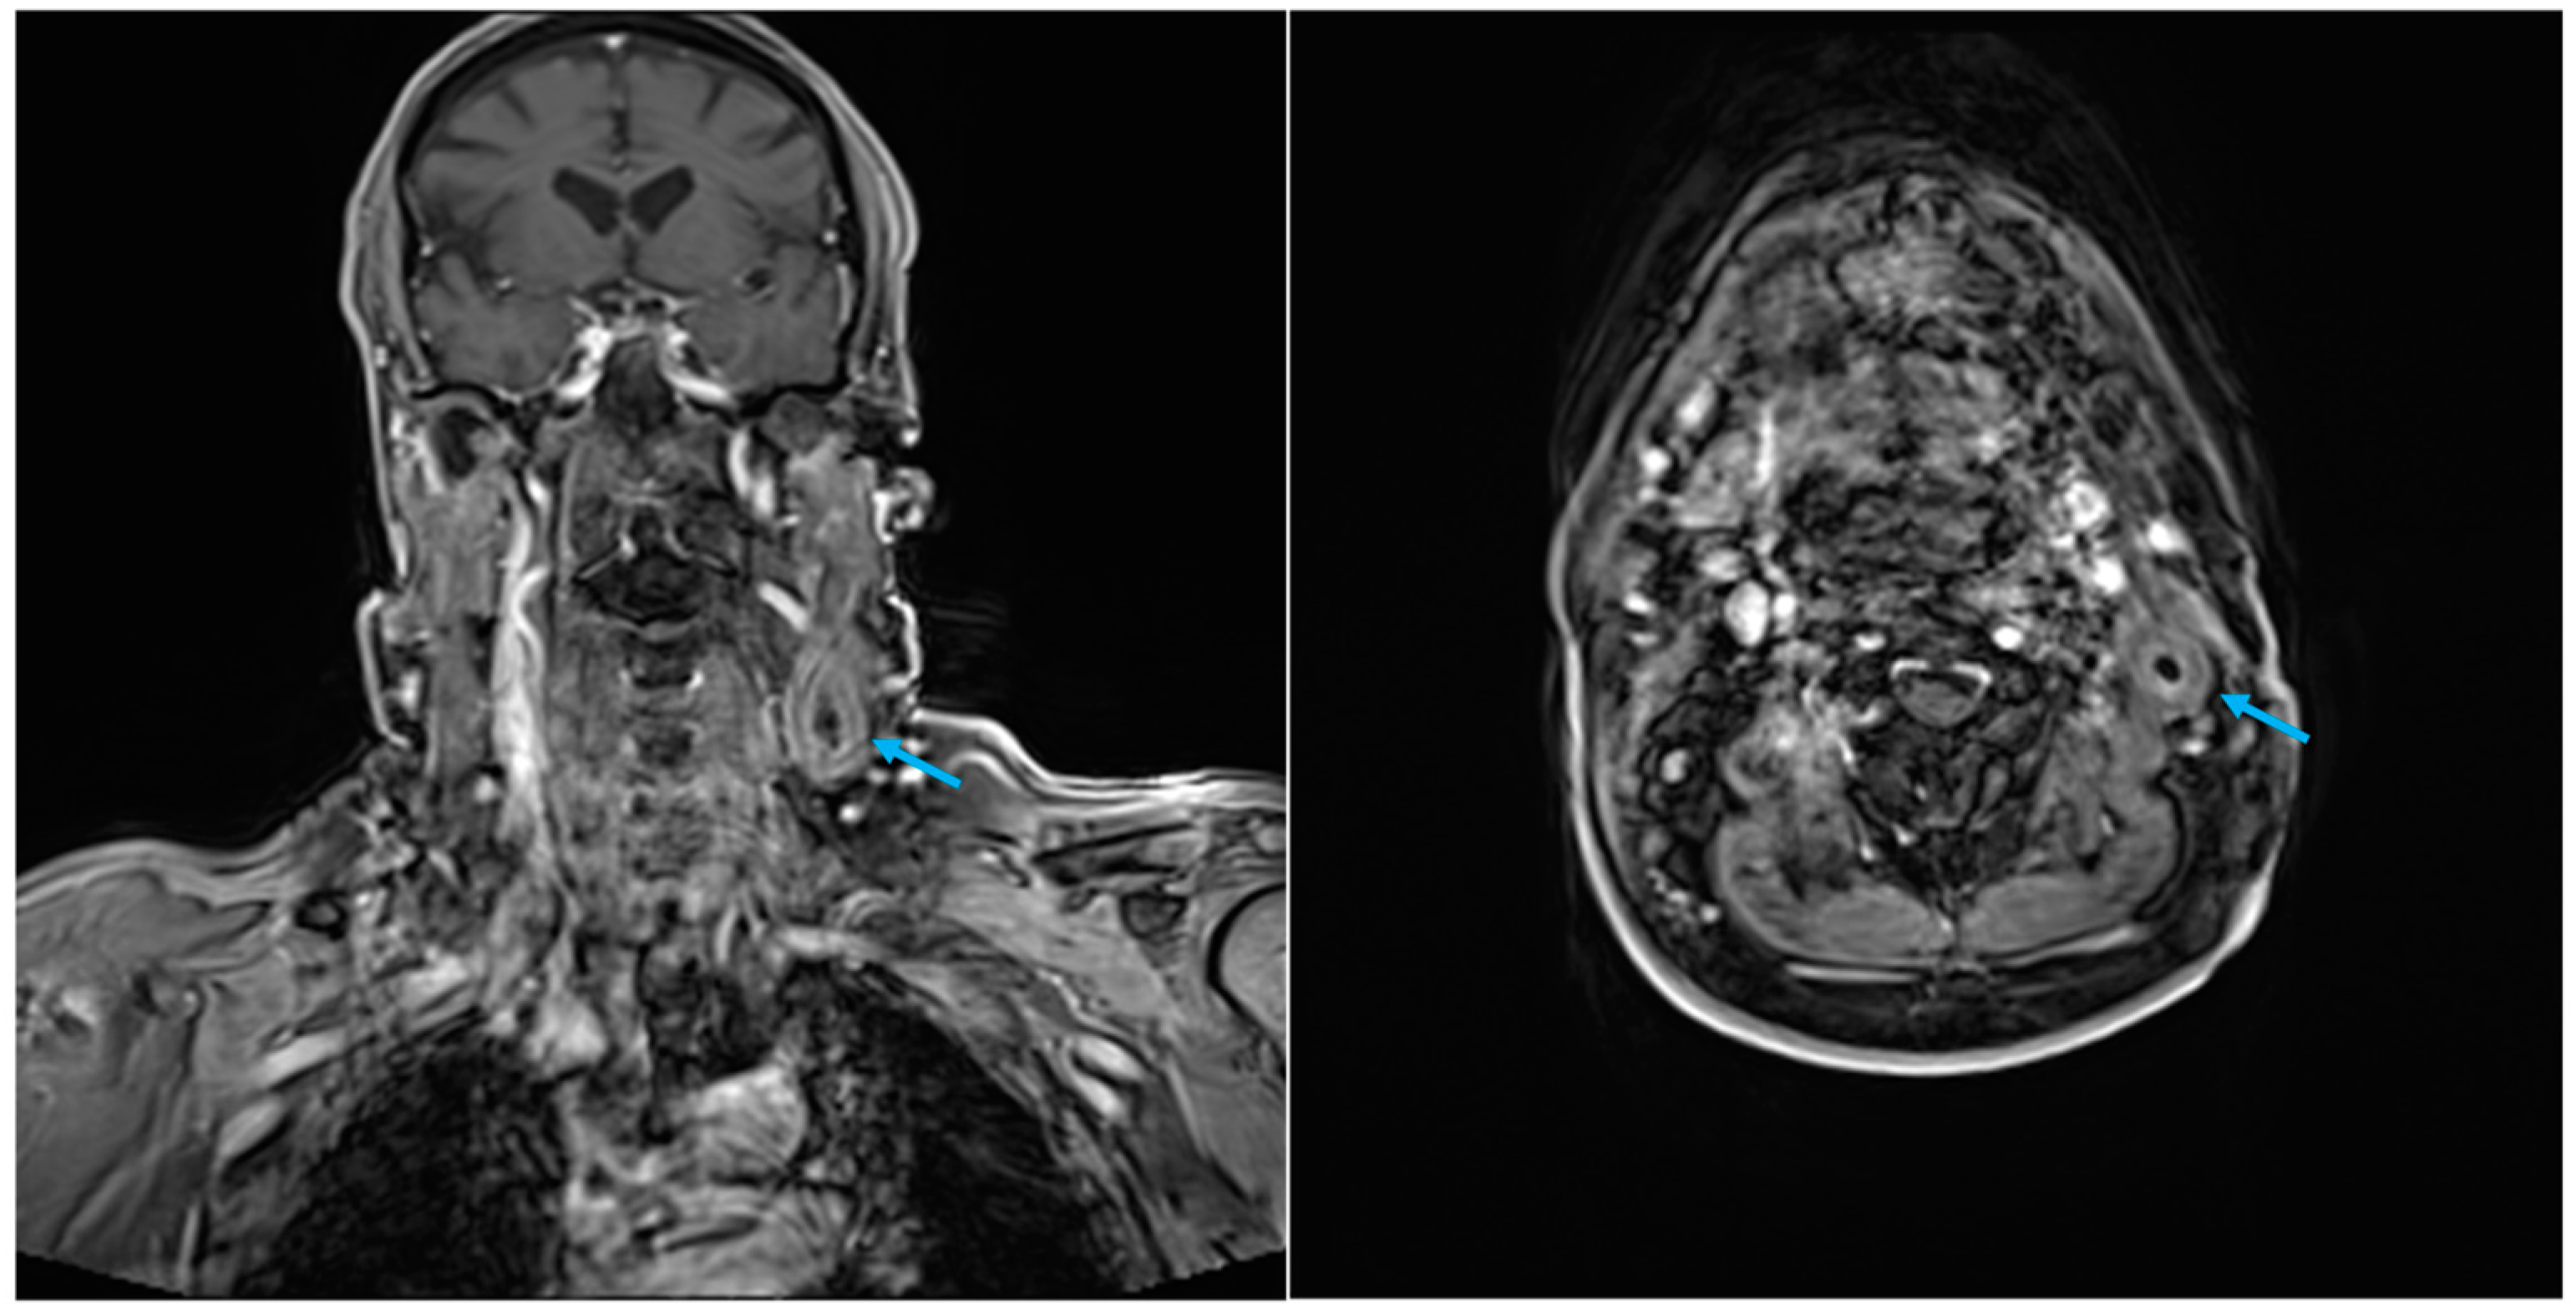

| Presented case 1 | 2024 | Case report | 1 | 78 | F | Maxilla | Tabotamp | Ameloblastoma | Excision of primary tumour | CT + MRI | 15 d | CT + MRI + surgical excison | H |

| Case 1 | Elongated, non-homogenous hyperechogenic formation with an expansive growth pattern | CT (1): Lymphadenopathy […] and exhibited areas of colliquation | Persistent left adenopathy was observed, with no evidence of restricted signal in DWI or post-contrastographic enhancement | Ovoid mass with an elevate 18-FDG uptake (SUV 7, 5) | C (1): Necrotic debris, neutrophilic granulocytes, and rare multinucleated histiocytic giant cells. C (2): Cytological sample revealed the presence of a birefringent material, which was identified as sutures, macrophages, and isolated foreign body-like giant multi-nucleated cells | |